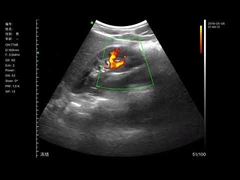

Kalite Portatif Ultrason tarayıcı, taşınabilir ultrason tarayıcı manufacturer from China